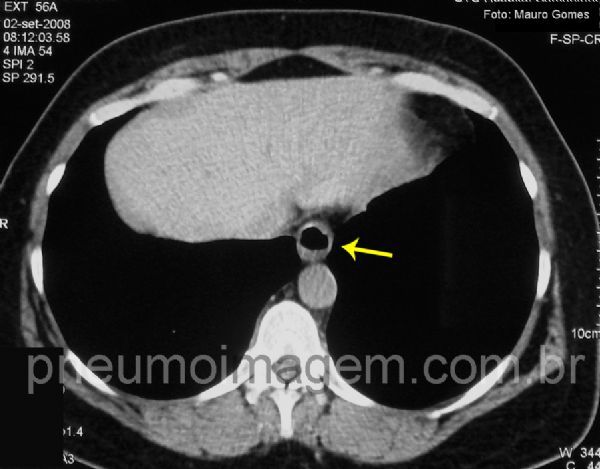

Pequena hérnia hiatal (seta amarela) sugerindo a presença de refluxo.

As manifestações pulmonares da DRGE podem ocorrer em qualquer região dos pulmões, dependendo do decúbito assumido pelo paciente ao dormir.

A BOOP faz parte das lesões pulmonares subagudas por aspiração, juntamente com a bronquiolite aspirativa difusa e a granulomatose miliar (esta associada à aspiração de partículas vegetais).

Small hiatal hernia (yellow arrow) suggesting the presence of reflux.

The pulmonary manifestations of GERD can occur in any region of the lungs, depending on the patient recumbent position while sleeping.

The BOOP is part of subacute pulmonary lesions by aspiration together with the aspiration diffuse bronchiolitis and miliary granulomatosis (associated to aspiration of vegetable particles).